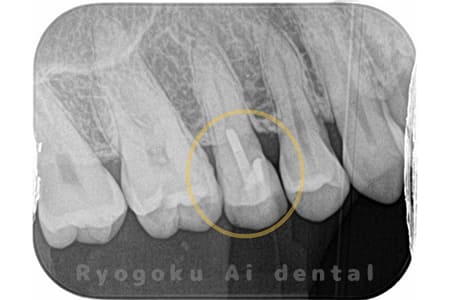

Case02

虫歯の治療と銀歯のやり直しを希望され、銀歯を外したところ、虫歯が大きく、神経の処置が必要と判断。患者様と相談し、神経を残す断髄治療となったケース。

<リスク・副作用>

術後は痛み、腫れ、痺れなどの副作用が生じる場合があります。症状が再発する可能性があります。その場合は抜髄する必要があります。